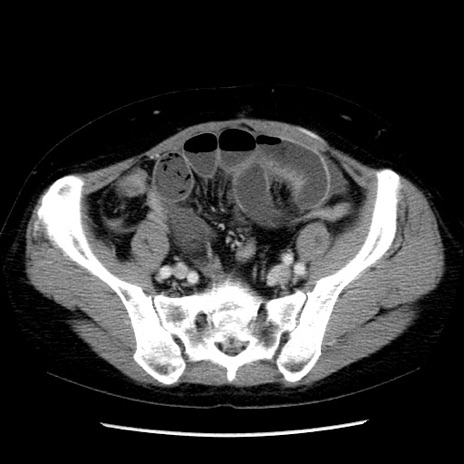

症例6(横断像)

【症例】50歳代女性

【主訴】下腹部痛

【現病歴】本日朝より下痢2回あり。 昼食を食べた後、嘔吐3回、下腹部痛認め、症状軽快せず、当院救急搬送。

【既往歴】卵巣癌術後(8年前に当院で卵巣摘出)

【身体所見】 意識清明、腹部:平坦、腸蠕動音→、やや硬、下腹部自発痛・圧痛あり、反跳痛あり、筋性防御なし。

【データ】WBC 16000、CRP 0.01